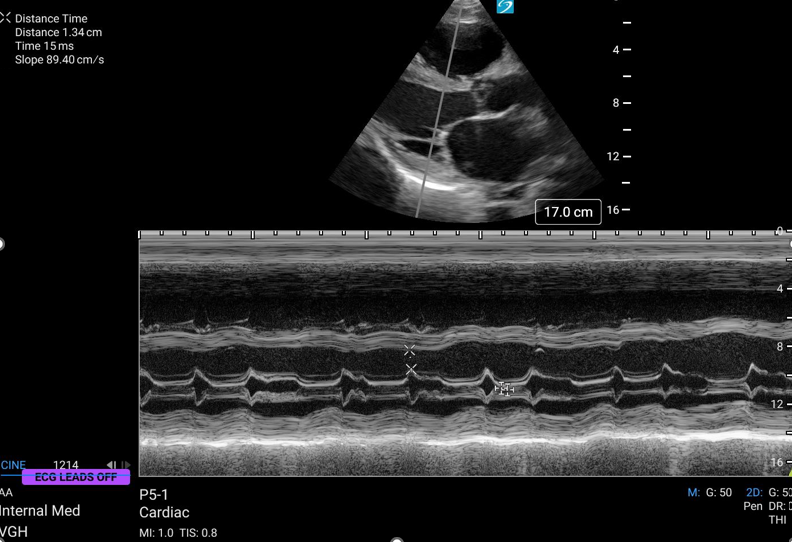

Cardiac ultrasound

EPSS